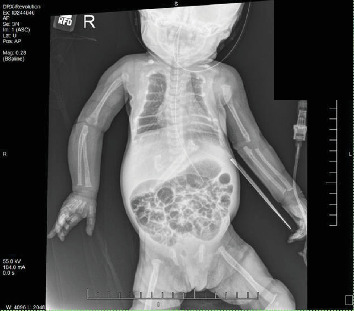

目的:描述一位患有新生儿严重甲状旁腺功能亢进(NSHPT)的女性新生儿的临床表现、诊断挑战和治疗的细节。方法:本病例报告来自回顾性图表回顾。该女婴为近亲父母所生,有多种产前问题,包括妊娠糖尿病、宫内生长受限、羊水过多、产前超声心动图(ECHO)怀疑左心房发育不良。在妊娠37周计划剖腹产后,新生儿表现出中度呼吸窘迫和肋下挛缩。体格检查时,发现颅骨裂、钟形胸部和持续的机械型杂音。结果:出生时的评估显示动脉导管未闭,骨骼结构明显脱矿,肋骨形态不典型。24 h血钙水平升高(14.3 mg/dL),血钙离子升高(2.32 mmol/L), 25-OH维生素D正常(54.2 ng/mL)。一项全面的骨骼调查发现了广泛性骨质减少、干骺端透明和骨折愈合的证据。在43 HOL下重复实验室工作,显示血清钙18.0 mg/dL, iCal 2.67 mmol/L,甲状旁腺激素(PTH)升高2116 pg/mL。NSHPT的诊断基于实验室结果。分子检测证实一个纯合子变异(c.1744T > a;p.Cys582Ser)在钙敏感受体(CaSR)基因中表达,证实了NSHPT的诊断。NSHPT是一种与高死亡率相关的罕见遗传疾病,通常由CaSR基因变异失活引起。患者家族史显示与家族性低钙血症高钙血症(FHH)密切相关,FHH是一种良性疾病,与无症状高钙血症相关,甲状旁腺水平正常至最低限度升高,低钙尿,由CaSR基因杂合失活突变引起。治疗NSHPT通常包括全甲状旁腺或次全甲状旁腺切除术;然而,最初的医疗干预往往是必要的。在此病例中,在成功切除甲状旁腺之前,新生儿接受了降钙素、速尿和静脉输液治疗,以帮助肾脏清除钙。结论:该病例强调了考虑具有复杂临床表现的新生儿罕见遗传疾病的重要性,并肯定了全面咨询和教育的必要性,特别是在近亲父母中,以解决家庭影响并指导适当的干预措施。

Objectives: Describe the details of the clinical presentation, diagnostic challenges, and management of a female neonate with neonatal severe hyperparathyroidism (NSHPT). Methods: This case report was developed from a retrospective chart review. The female infant was born to consanguineous parents-first cousins, with multiple prenatal concerns, including gestational diabetes, intrauterine growth restriction, polyhydramnios, and suspicion of a hypoplastic left atrium on prenatal echocardiogram (ECHO). Following a planned C-section at 37 weeks gestation, the neonate exhibited moderate respiratory distress with subcostal retractions. On physical examination, craniotabes, a bell-shaped chest, and a continuous machinery-type murmur were noted. Results: Evaluation at birth revealed a large Patent Ductus Arteriosus and significant demineralization of skeletal structures with atypical rib morphology. Lab work at 24 h of life (HOL) showed elevated serum calcium level (14.3 mg/dL), ionized calcium-iCal (2.32 mmol/L), and normal 25-OH Vitamin D (54.2 ng/mL). A comprehensive skeletal survey uncovered generalized osteopenia, metaphyseal lucencies, and evidence of healing fractures. Repeat lab work at 43 HOL, showed serum calcium of 18.0 mg/dL, iCal 2.67 mmol/L, and elevated parathyroid hormone (PTH) of 2116 pg/mL. Diagnosis of NSHPT was established based on laboratory findings. Molecular testing confirmed a homozygous variant (c.1744T >A; p.Cys582Ser) in the calcium-sensing receptor (CaSR) gene which confirmed the diagnosis of NSHPT. NSHPT, a rare genetic disorder associated with high mortality rates, is often caused by inactivating CaSR gene variants. The patient's family history revealed a strong correlation with familial hypocalciuric hypercalcemia (FHH), a benign condition associated with asymptomatic hypercalcemia, normal to minimally elevated parathyroid level, and hypocalciuria, it is caused by heterozygous inactivating mutations in the CaSR gene. Treatment of NSHPT typically involves total or subtotal parathyroidectomy; however, initial medical intervention is often necessary. In this case, the neonate underwent medical treatment with calcitonin, furosemide to help facilitate renal clearance of calcium, and intravenous fluids before a successful parathyroidectomy. Conclusions: This case accentuates the importance of considering rare genetic disorders in neonates with complex clinical presentations and affirms the need for comprehensive counseling and education, particularly in consanguineous parents, to address familial implications and guide appropriate interventions.